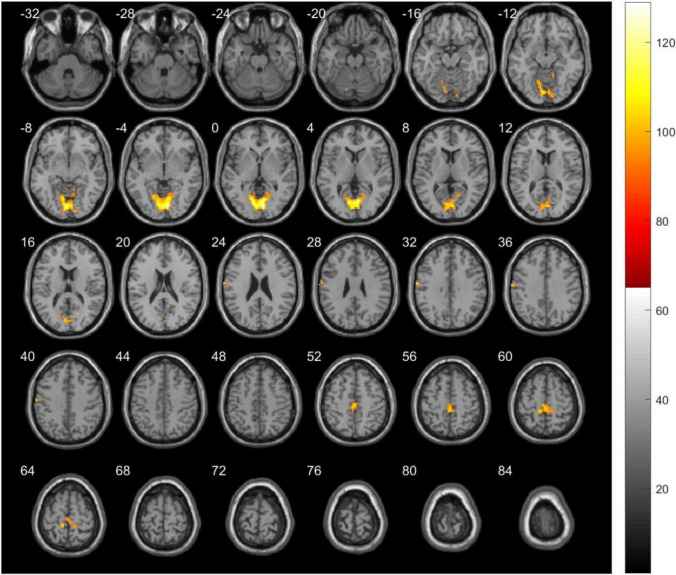

To characterize local functional connectivity (FC) differences in children with autism spectrum disorder (ASD) compared to typically developed (TD) children, and to analyze the correlation between local FC and the atypical behavior in autistic children. Thirty children with ASD and 25 TD children were recruited. Participants underwent rs-fMRI scans, and regional homogeneity (ReHo) of specific brain regions was measured. Performance was assessed using the Autism Behavior Checklist (ABC) and the Gesell Development Diagnosis Scale (GDDS). Children with ASD demonstrated reduced ReHo in the right occipital lobe lingual, left postcentral, and left precuneus compared with TD children. Within the ASD group, the ABC total score was negatively related to ReHo values in both the left postcentral and left precuneus. The ReHo value in the left postcentral was negatively correlated with ABC scores related to sensory and body/object use, while the ReHo value in the left precuneus was negatively correlated with scores related to social skills and self-help. The mean Developmental Quotient (DQ) of GDDS was positively correlated with the ReHo value in the right occipital lobe lingual. Besides, the ReHo value in this region was positively correlated with the DQ of adaptive behavior. The ReHo value in the left postcentral was positively correlated with the DQ of fine motor skills (p < 0.05 for all). Children with ASD exhibit reduced local FC in specific brain regions, which are associated with specific performances in autism. These findings may provide a novel insight into the pathophysiological mechanisms of ASD.